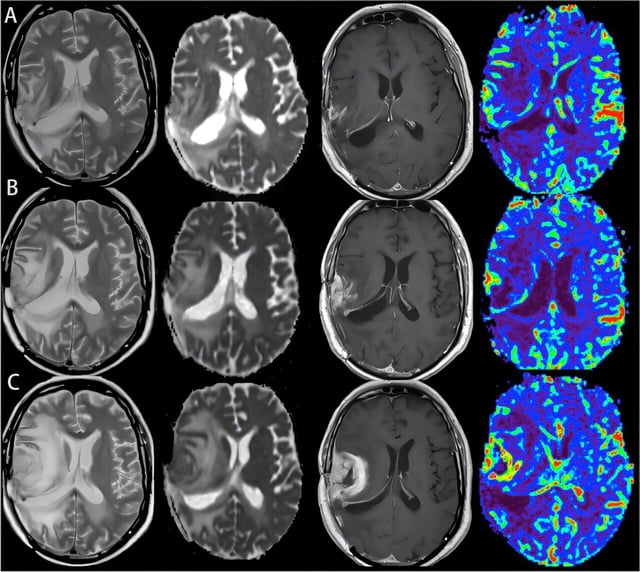

• Researchers at Montefiore Einstein and Albert Einstein report in Nature Neuroscience that glioblastoma thins calvarial bone and enlarges skull–brain channels in mouse models, with focal skull thinning corroborated on patient CT scans.